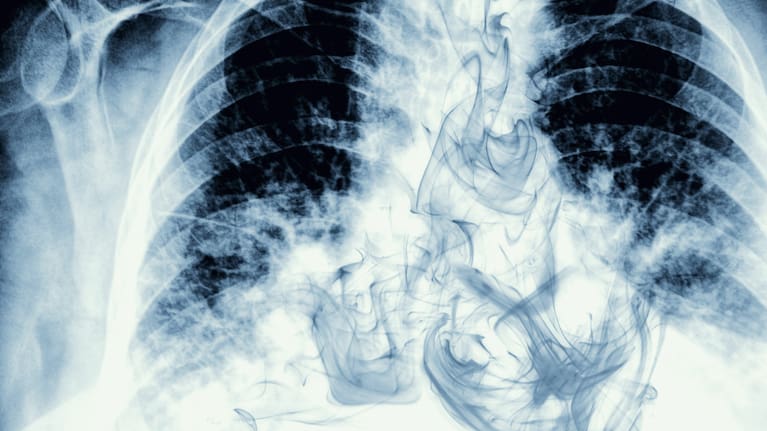

A study conducted by Ottawa Hospital in Canada examined the chest CT examinations of 56 cannabis smokers, 57 non-smokers, and 33 tobacco-only smokers between 2005 and 2020.

The researchers reported three-quarters (75%) of cannabis smokers had emphysema - a lung disease that causes difficulty with breathing - compared with 67% of tobacco-only smokers.

Only 5% of the non-smokers had emphysema.

Compared to the Canadian study, a New Zealand cross-sectional study found people who exclusively smoked cannabis were much less likely to show evidence of emphysema on high-resolution CT scans than tobacco smokers, suggesting that macroscopic emphysema is not a common consequence of cannabis use.